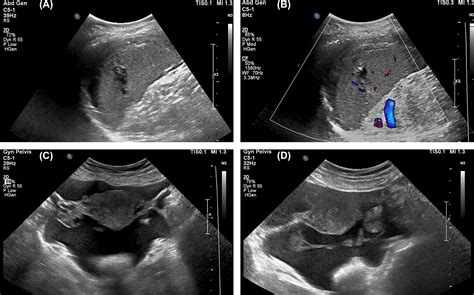

• Imaging Tests: Imaging tests such as CT scans are crucial for visualizing the spleen and assessing the extent of the injury. These tests provide detailed images that help in Splenic Laceration Grading.